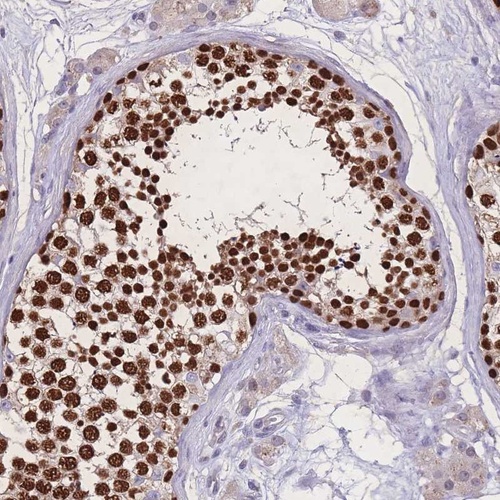

Immunohistochemical staining of human testis shows strong nuclear positivity in cells in seminiferus ducts.